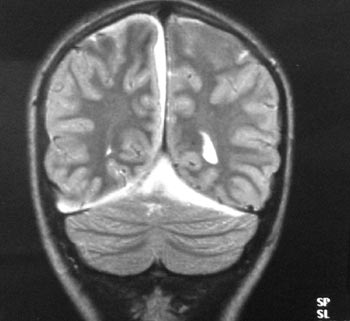

Εικόνα 4. MRI (3ο

24ωρο): εκτεταμένη συλλογή πύου στη μεσοημισφαιρική σχισμή και πάνω από τα παρεγκεφαλιδικά

ημισφαίρια.